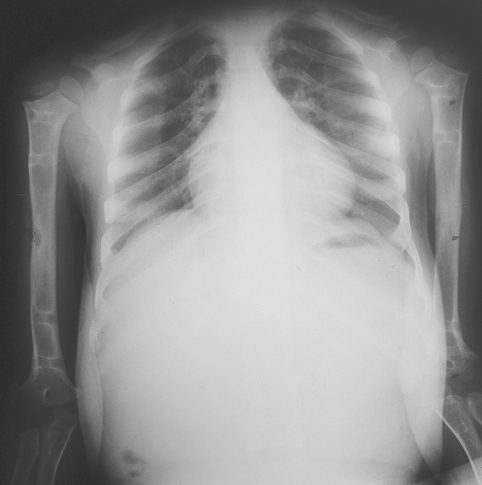

Vaka 1